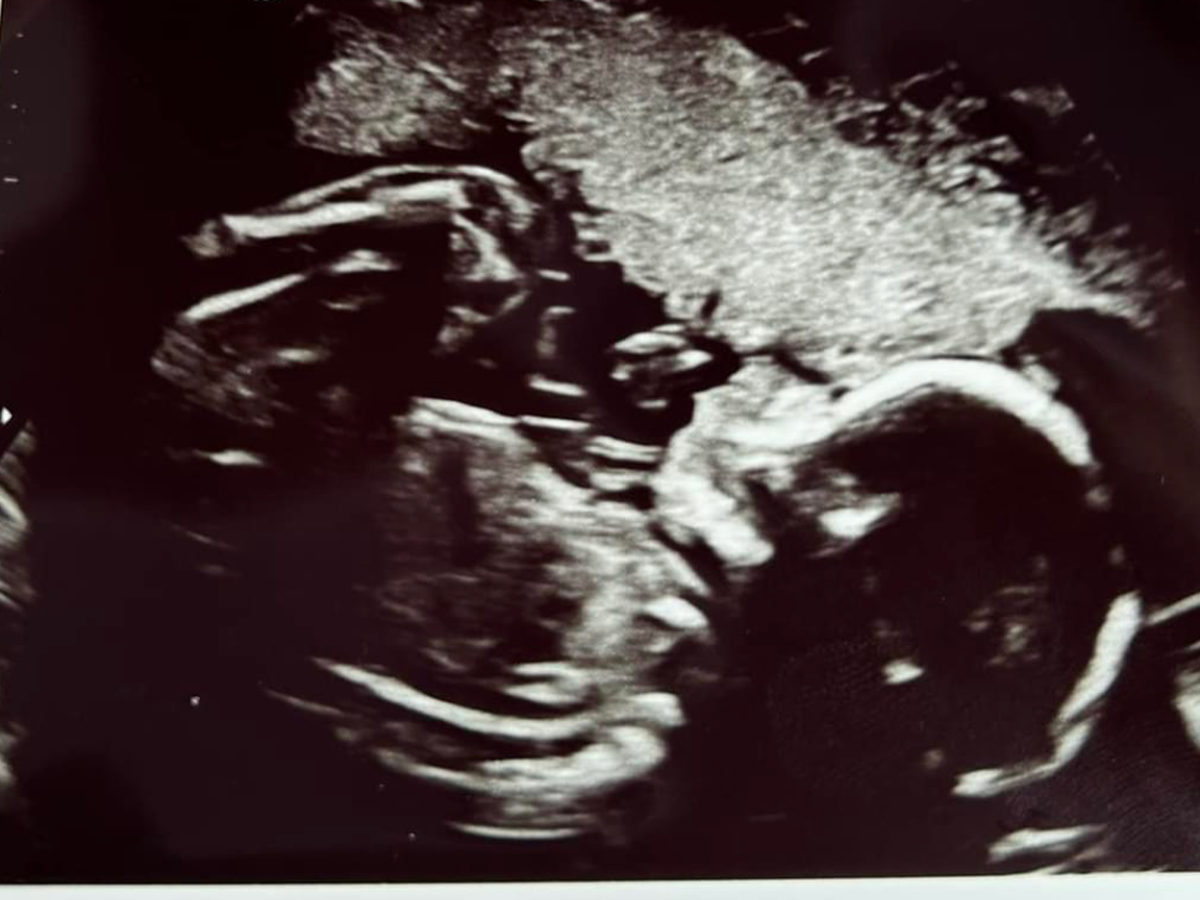

Hi my name is Todd Dudley and my wife Alexis and I are setting this up to help with expenses when our daughter is born late September. Our daughter Rosalie has been diagnosed with a congenital heart defect called transposition of the greater arteries which means the two major arteries of her heart are switched and because of this she will not be able to oxygenate her body when she is born and will need open heart surgery within a few days after birth. This surgery will require the surgeon to go in and switch these two arteries and reattach them to the correct sides of the heart. They also have to move the coronary arteries as well which is the tricky part. Anything would help us with living expenses, travel, food, and medical bills associated with her having to stay in UVA NICU and Cardiac ICU for 3 weeks to a month. My wife will be staying up there the whole time and I’ll have to travel back and forth and take care of our 20 month old. We really appreciate any help so we don’t have to stress about bills while we are already extremely worried for our daughter and her recovery. If you can’t donate we ask for continued prayers for a successful surgery and speedy recovery. God bless!